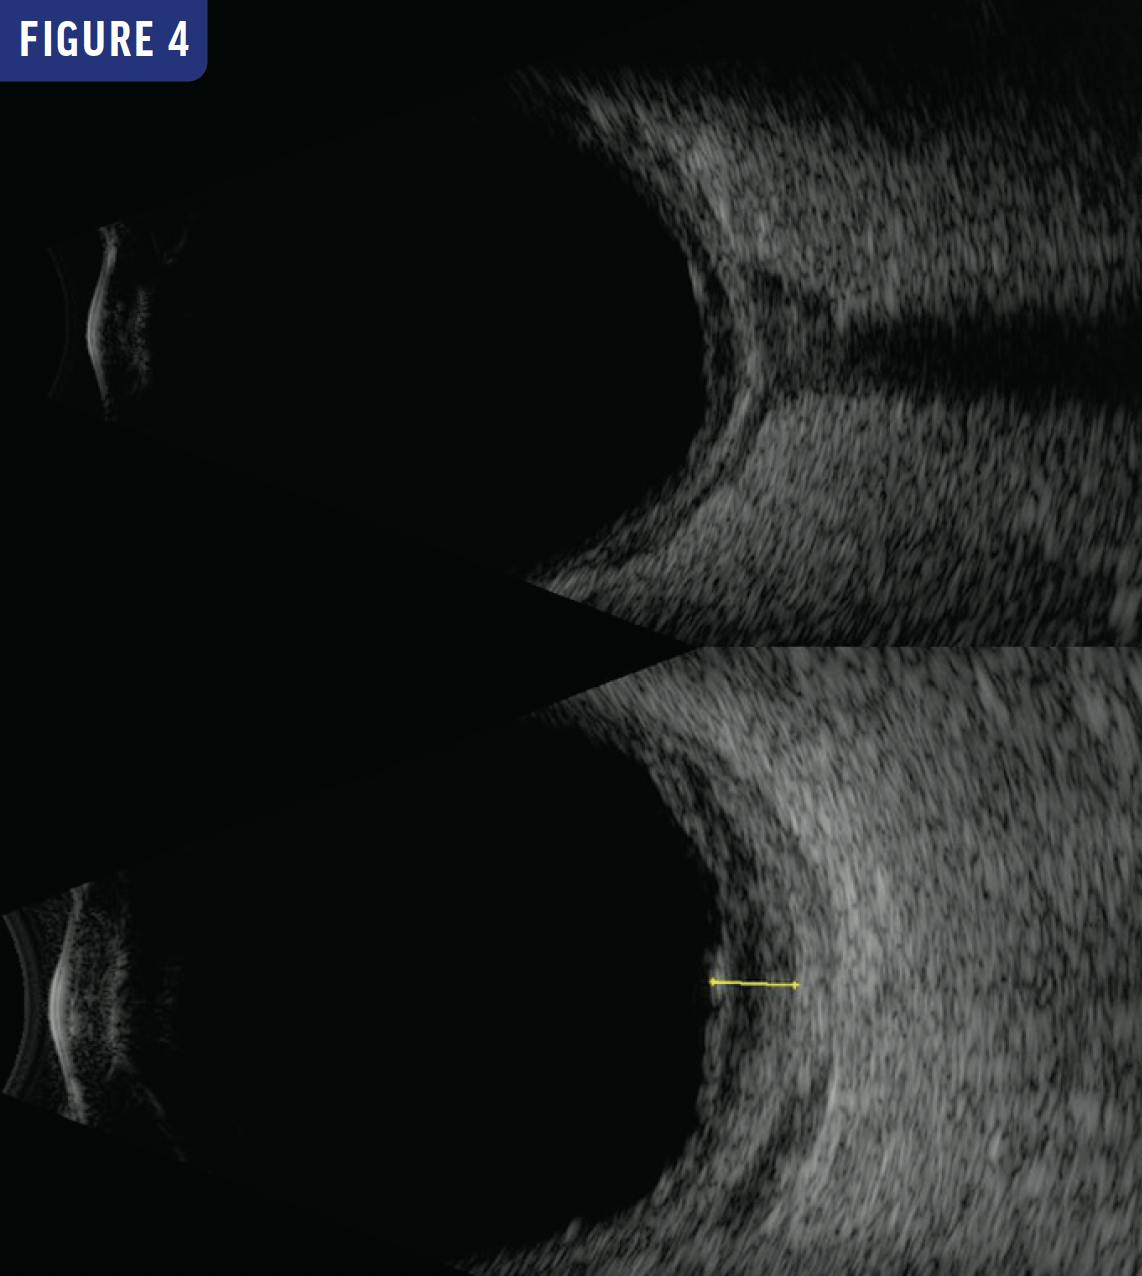

ICG angiography showed hypofluorescence corresponding to the choroidal lesions in the right eye. Fluorescein angiography showed early peripapillary blockage with late staining of the lesion in the right eye (Figure 2). Macular OCT showed choroidal elevation with an intact overlying retina and scattered subretinal hyperreflective lesions (Figure 3). B-scan ultrasonography showed peripapillary fundus thickening (Figure 4).

The workup was positive for prior exposure to toxoplasmosis (IgG positive and IgM negative), and MRI showed asymmetric thickening of the right retina and choroid. Given the otherwise negative workup, the most likely diagnosis was reactive lymphoid hyperplasia of the uvea. The patient was subsequently followed for 6 years with stable appearance of the lesions and visual acuity.